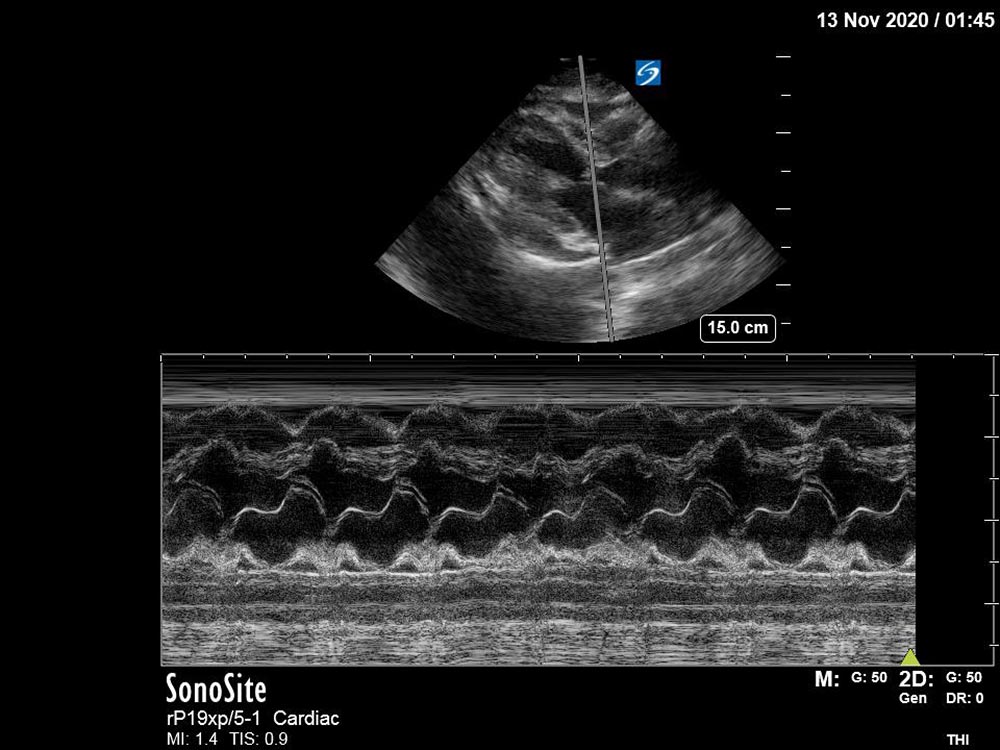

An elderly patient with multiple co-morbidities presents to the ED with dyspnea and is found to be in obstructive shock secondary to cardiac tamponade. The learner should perform a primary survey, recognize the need for emergent intervention, and rapidly obtain key diagnostic data, including performance of a bedside ultrasound. Upon recognizing that the patient has cardiac tamponade, appropriate management should be initiated, including resuscitation and emergent pericardiocentesis.